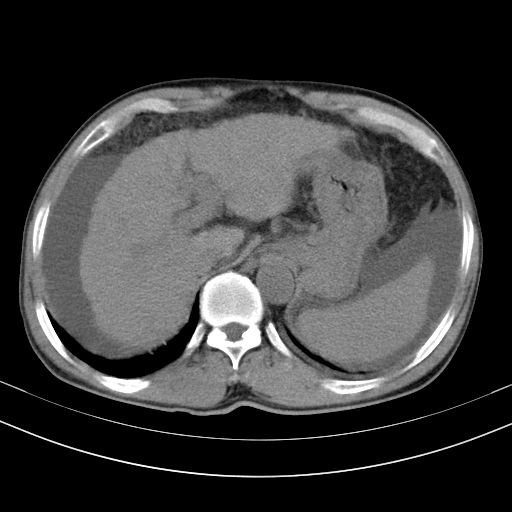

以下是引用随光逐影在2010-2-28 10:23:00的发言:[br]1)考虑肝癌;建议行ct增强扫描检查。2)肝硬化,脾大,腹水。3)慢性胆囊炎。